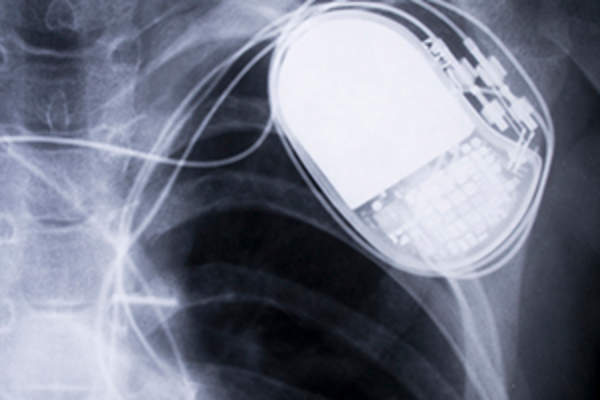

起搏器可能是临时的,也可能是永久性的,内部或外部的电池发电机和引线(导线)在皮下。这些导线发送电子信息,使心肌有规律地收缩。相反,除颤器同时提供低冲击重置心律不齐和更大的冲击来对付危险的室性心律失常。像心脏起搏器,心脏除颤器使用电池和导线进入心脏,但设备在胸部或腹部皮肤下放置。

ICD的优点和缺点

对于那些心律失常损害正常功能并增加死亡率的患者来说,ICDs是一种令人惊奇的工具,可以在日常情况和锻炼中提供平静的心情。手术中插入该设备被认为是微创性的,而不是开胸。然而,icd并非没有风险:它们可能不正确地传递电击,而且在植入部位可能会感染。特别是在一些患者中使用ICD那些没有其他心脏疾病,可能对死亡率没有什么好处。